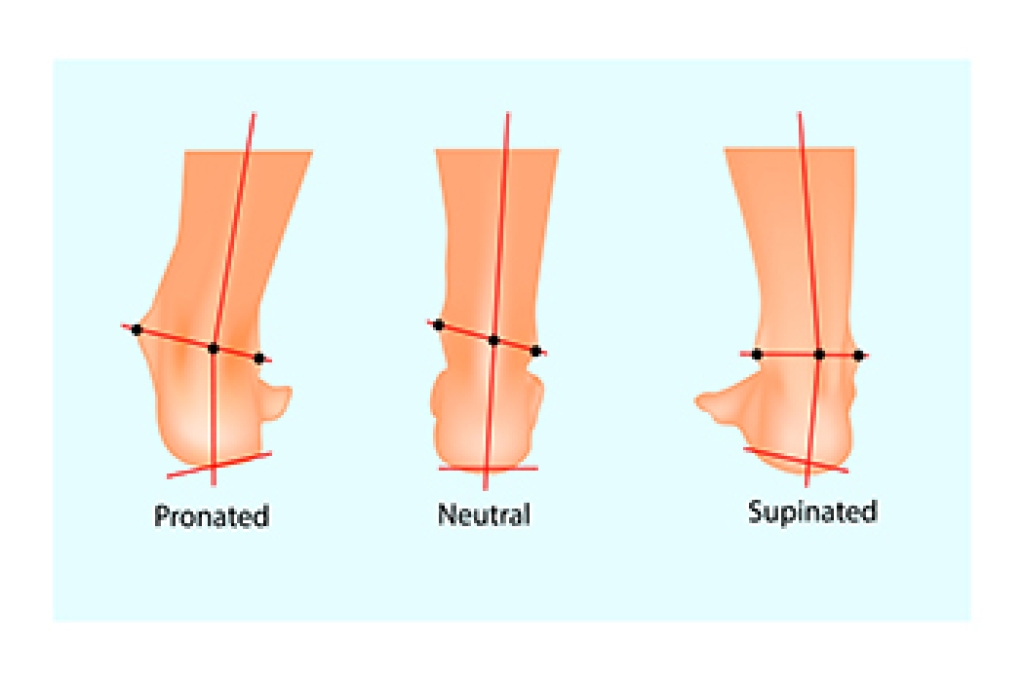

Can Overpronation Be Corrected?

Overpronation, a common foot condition involving excessive inward rolling, requires careful attention to alleviate symptoms and prevent complications. The primary approach to overpronation involves adopting supportive footwear, which may include specialized shoes to minimize excessive movement and provide stability in the heel and midfoot. For those with moderate to severe overpronation, custom orthotics, tailored to the individual's foot shape, provide personalized assistance in reducing overpronation. Targeted exercises are believed to help in correcting overpronation. The short-foot exercise, involving lifting the arch of the foot off the ground, is particularly beneficial in addressing overpronation. In rare cases of severe overpronation, surgical intervention may be necessary. Reconstruction surgery aims to realign bones, providing better arch support, and may involve the use of stabilizing metal implants. If overpronation affects your well-being, it is suggested that you make an appointment with a podiatrist for a gait analysis, examination, and a treatment plan targeted to your particular condition.

If you have any concerns about your feet, contact Edward Orman, DPM from Honeygo Podiatry. Our doctor can provide the care you need to keep you pain-free and on your feet.

Biomechanics in Podiatry

Podiatric biomechanics is a particular sector of specialty podiatry with licensed practitioners who are trained to diagnose and treat conditions affecting the foot, ankle and lower leg. Biomechanics deals with the forces that act against the body, causing an interference with the biological structures. It focuses on the movement of the ankle, the foot and the forces that interact with them.

A History of Biomechanics

- Biomechanics dates back to the BC era in Egypt where evidence of professional foot care has been recorded.

- In 1974, biomechanics gained a higher profile from the studies of Merton Root, who claimed that by changing or controlling the forces between the ankle and the foot, corrections or conditions could be implemented to gain strength and coordination in the area.

Modern technological improvements are based on past theories and therapeutic processes that provide a better understanding of podiatric concepts for biomechanics. Computers can provide accurate information about the forces and patterns of the feet and lower legs.

Understanding biomechanics of the feet can help improve and eliminate pain, stopping further stress to the foot.

If you have any questions please feel free to contact our offices located in Perry Hall, and Fallston, MD . We offer the newest diagnostic and treatment technologies for all your foot and ankle needs.